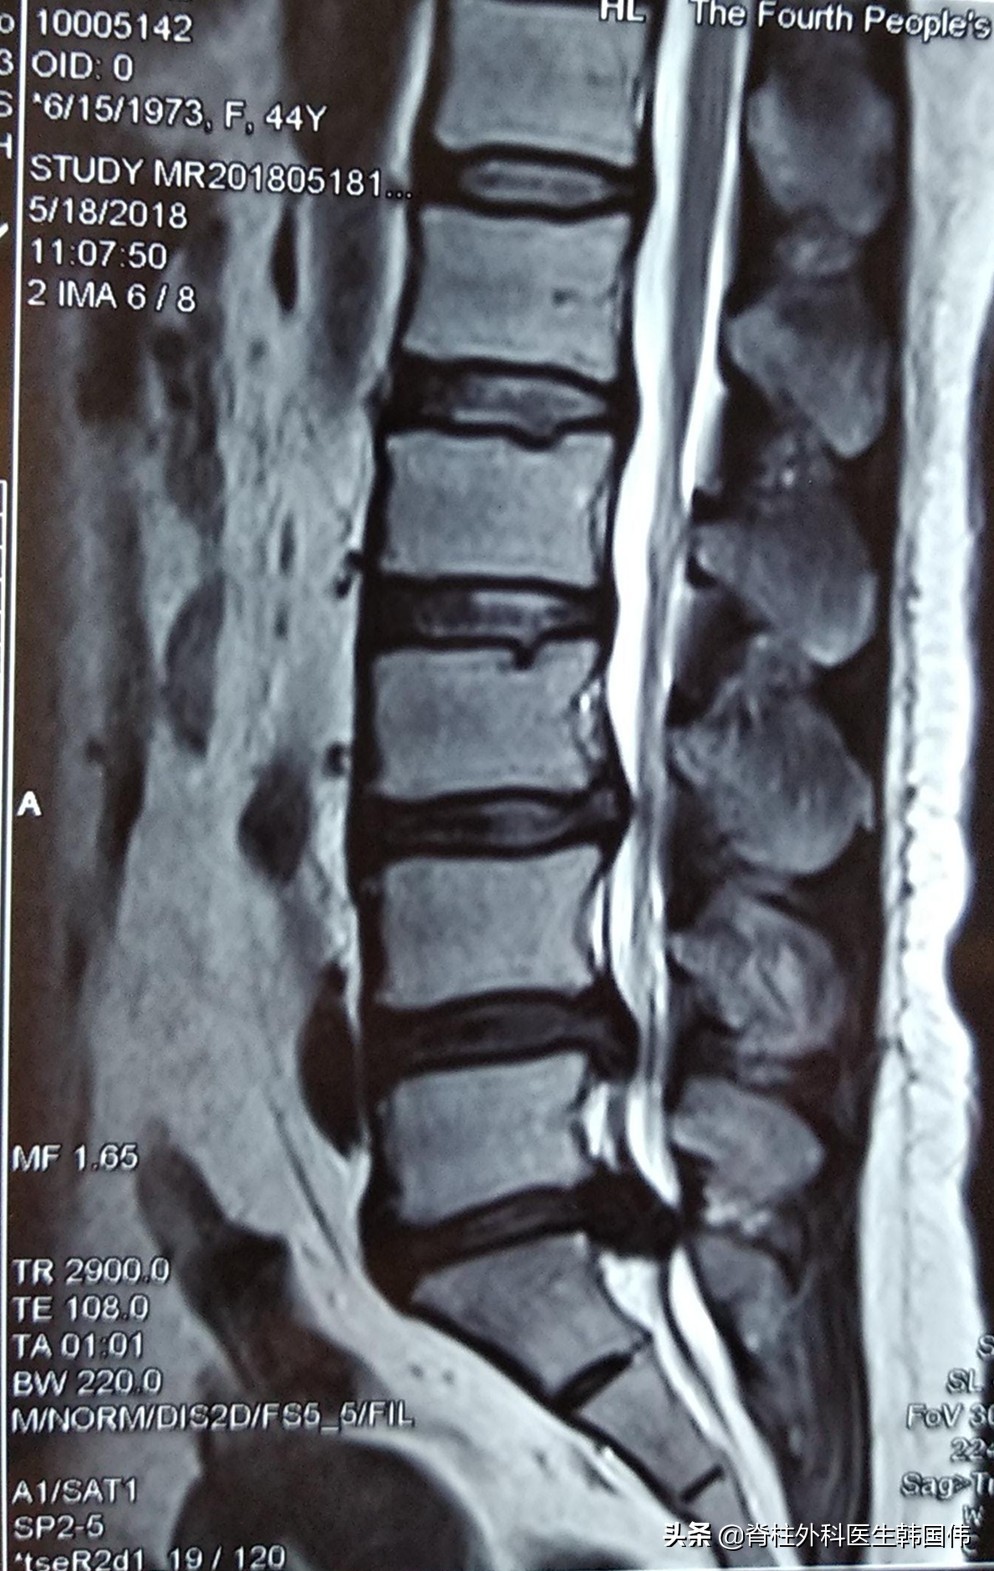

一般而言,通过腰椎核磁共振检查可以看出患者是否存在髓核脱出的情况,以及髓核在椎管中的位置。